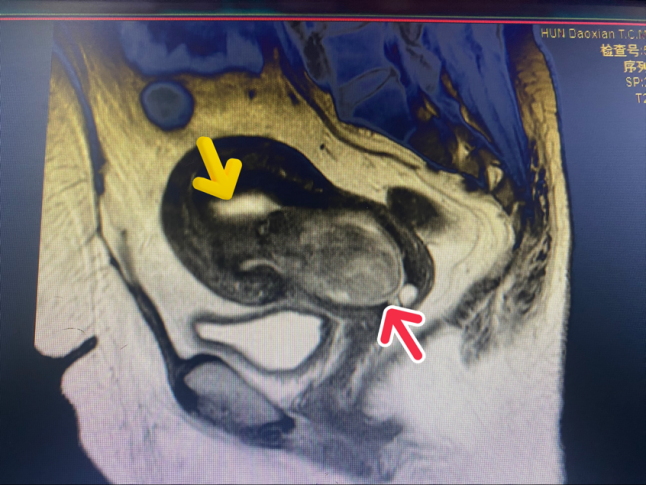

(通讯员:张义之) 患者何女士39岁,因异常阴道流血到道县中医医院妇产科门诊就诊。B超检查提示:宫腔下段高回声结节(69*37mm)。检查后初步诊断:子宫粘膜下肌瘤。患者合并有上呼吸道感染及糖尿病,门诊医生评估患者情况后收住院治疗。

住院期间,经内分泌科会诊后控制患者血糖情况,并完善术前准备工作。妇产科主任何娉娟副主任医师带领团队,为患者行宫腔镜下子宫黏膜下肌瘤电切术,严格按照“切割、钳夹、捻转、牵拉、娩出”五步法,顺利将患者宫腔内肌瘤切除干净,手术用时40分钟,术中出血仅5ml。术后予以中药外敷活血化淤、消癥散结等对症治疗,患者麻醉复苏后即可下床和常规饮食,无腹痛,阴道流血少,术后2天平安出院。